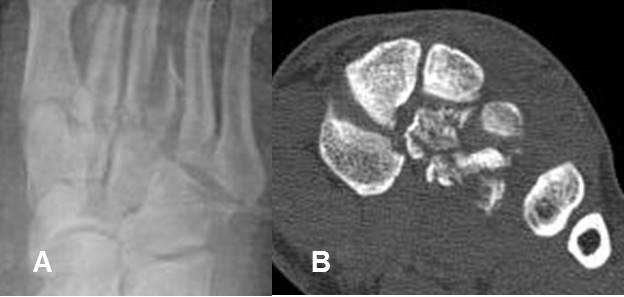

Fig 196. Fractura de Lisfranc.

A: Rx AP. Pérdida en la nitidez en las 2º y 3º articulaciones tarsometatarsianas, por fracturas no desplazadas en el plano AP.

B: TAC reconstrucción coronal. Fracturas conminutas en la cuña media y lateral, las cuales están desplazadas posteriormente.